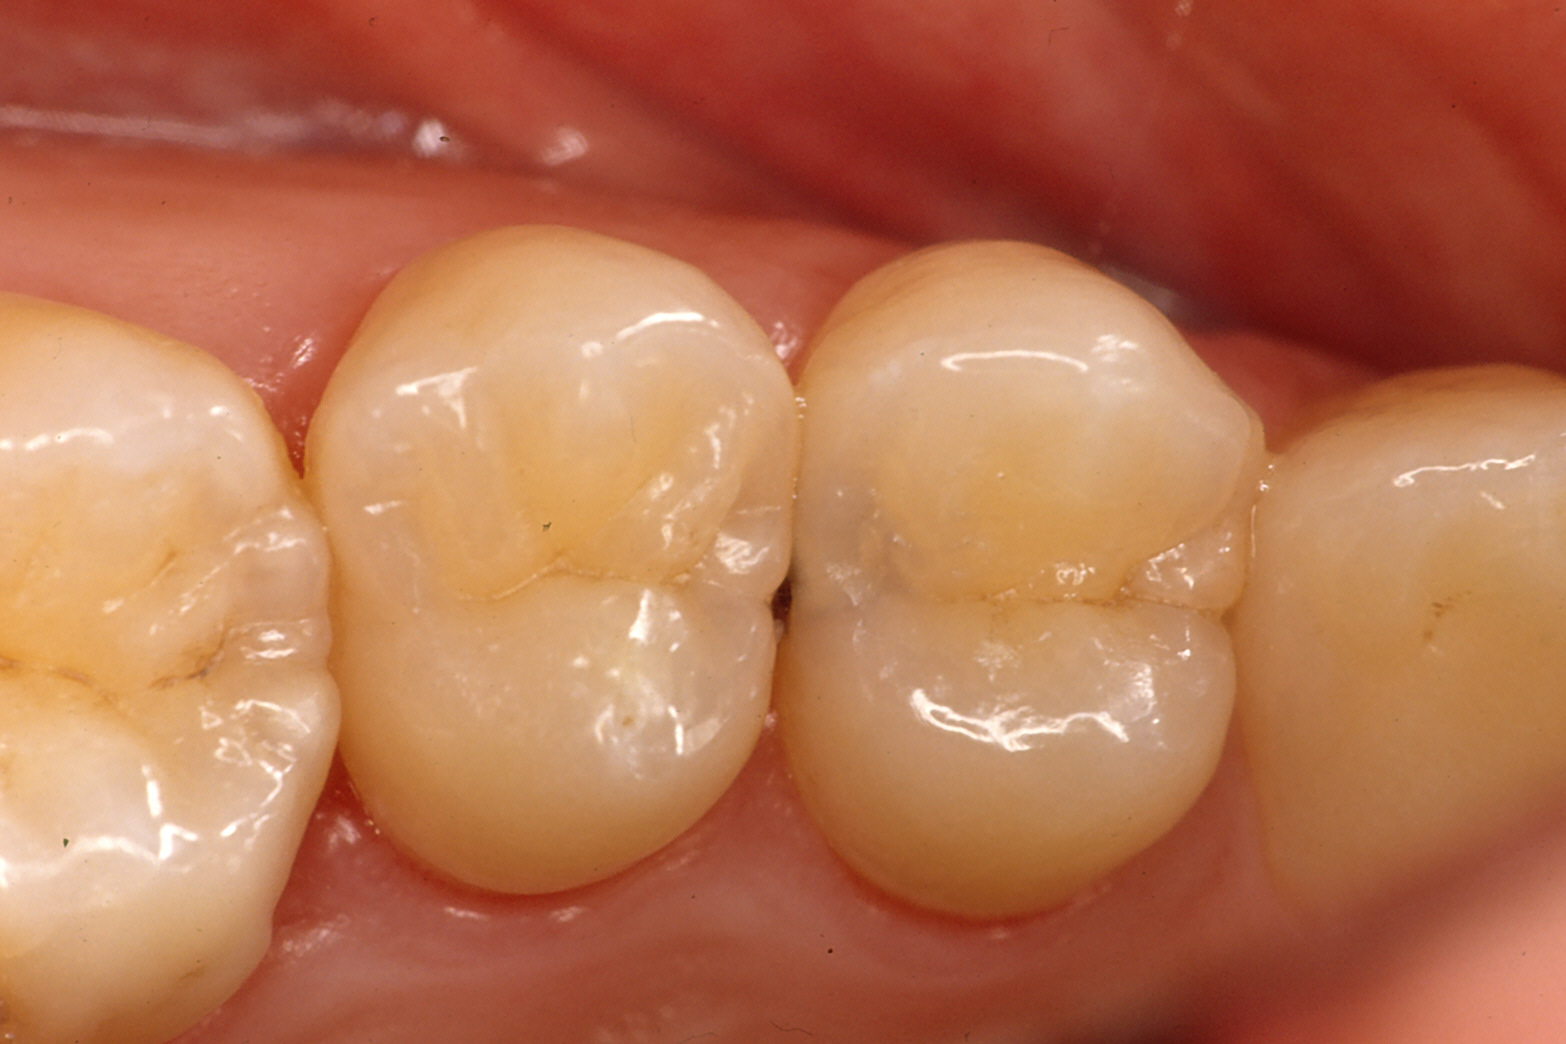

奥歯の治療

上の写真、穴が見えなくても大きな虫歯があります。

(金属で治す場合、下の写真のように削ります)

治療方法

- 金属を入れる

- 保険の白い詰め物で治す

- 保険外(自費)で白い物をはめる(ポーセレンインレー等)

それぞれに利点欠点があります。虫歯の状況だけでなく、かみ合わせ、口腔内環境、習慣等々から総合的に判断しお勧めします。